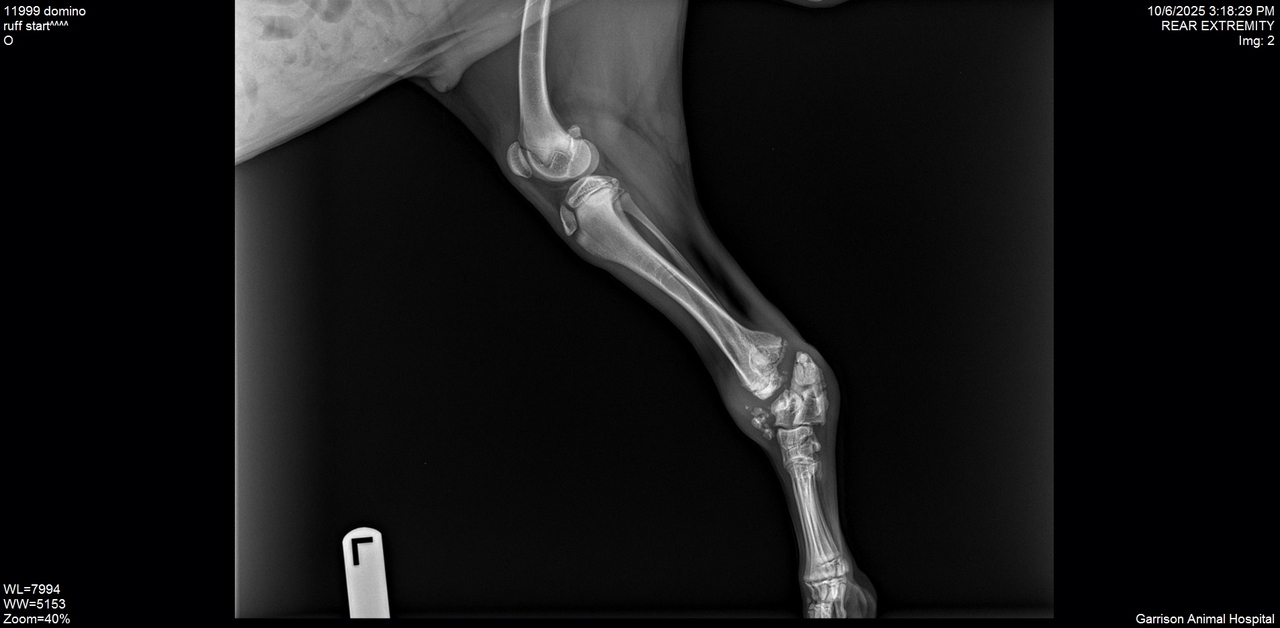

But soon after arriving, it became clear something wasn’t right. An exam and x-rays revealed a chronic, unrepairable fracture in his back leg - leaving amputation as the best path forward for a pain-free future.